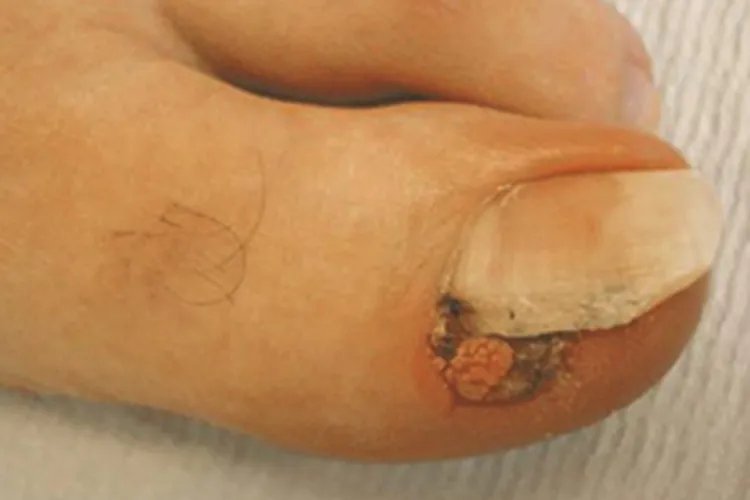

寻常疣脚趾甲肉球图片

的有关信息介绍如下:寻常疣可发生在脚趾甲部位,典型皮损为黄豆大小或更大的丘疹性肉球,表面似杨梅样有密集的颗粒状突起,疣体向甲下发展,可破坏甲床,引起感染,导致甲沟炎,趾甲侧缘有红肿,患者自觉有明显疼痛。部分严重的可呈乳头瘤状增生。